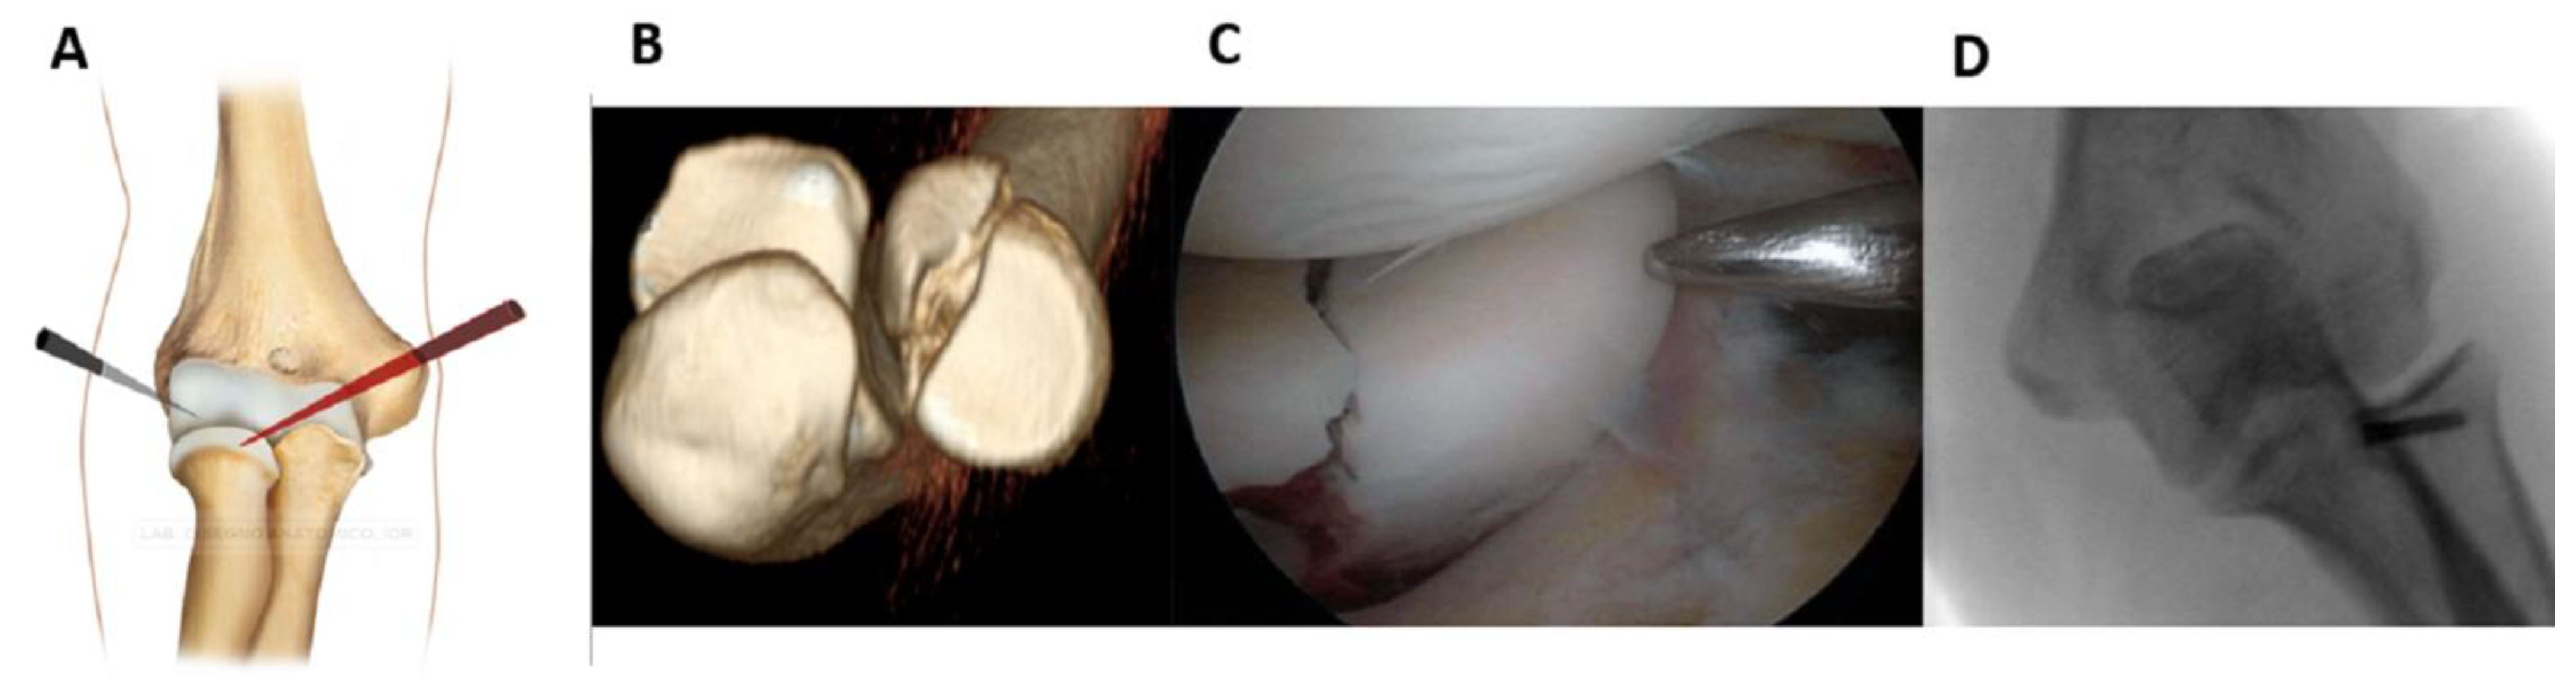

Fractures of the lateral half can be fixed from the anterolateral portal (working position AL) by placing the forearm in pronation and examining from the AM portal (Figure 1).

Figure 1. Fractures of the lateral half can be fixed from the anterolateral working position (A). (B): pre-operative 3D CT scan showing the fracture. (C): intraoperative image of fracture fixation. (D): Control x-ray.